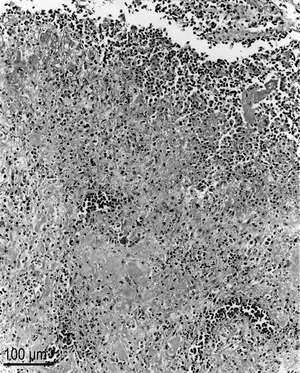

H&E stain

Hematoxylin and eosin stain or haematoxylin and eosin stain (H&E stain or HE stain) is one of the principal stains in histology. It is the most widely used stain in medical diagnosis and is often the gold standard; for example when a pathologist looks at a biopsy of a suspected cancer, the histological section is likely to be stained with H&E and termed "H&E section", "H+E section", or "HE section". A combination of hematoxylin and eosin, it produces blues, violets, and reds.

The staining method involves application of hemalum, a complex formed from aluminum ions and hematein (an oxidation product of hematoxylin). Hemalum colors nuclei of cells (and a few other objects, such as keratohyalin granules and calcified material) blue. The nuclear staining is followed by counterstaining with an aqueous or alcoholic solution of eosin Y, which colors eosinophilic structures in various shades of red, pink and orange.

The eosinophilic structures are generally composed of intracellular or extracellular protein. The Lewy bodies and Mallory bodies are examples of eosinophilic structures. Most of the cytoplasm is eosinophilic. Red blood cells are stained intensely red.

So, in optical microscopy we can observe :[1]

- Nuclei in blue/purple

- Cytoplasm in red

- Erythrocytes in cherry red

- Collagen in pale pink